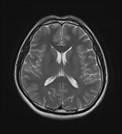

그림2.jpg 촬영 일시: 2025.06.11

<Fig 1. 정상 MRI 소견>